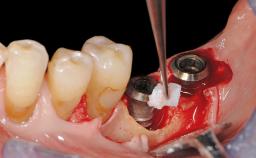

Resective Surgical Treatment of Peri-Implantitis Including Implantoplasty

In this case, Myroslav Solonko, Ignacio Sanz Sánchez and Mariano Sanz present a treatment that aims to eliminate exposed implant threads by modifying the implant surface, converting a moderately-rough surface into a smooth surface.